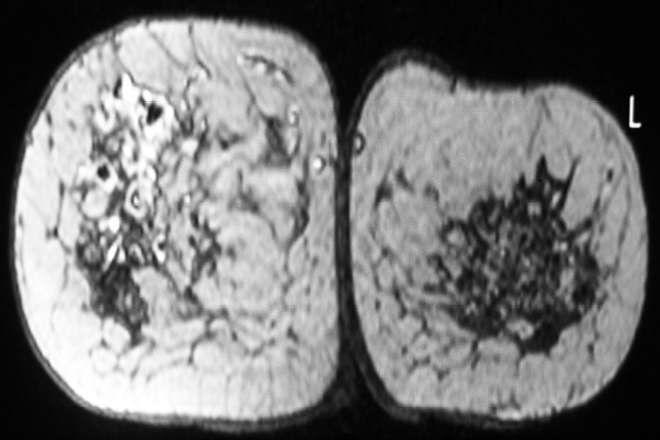

Entre sus antecedentes demográficos: nivel socioeconómico bajo; alimentación en suficiente cantidad, pero deficiente en calidad; escolaridad primaria completa; dedicada a labores del hogar; y sin antecedente de inmunización con BCG. El padecimiento actual lo inició tres meses previos al establecimiento del diagnóstico, con dolor en la región dorsal, de mediana intensidad, asociado con el tumor decúbito dorsal. Un mes después apareció uno en la mama izquierda, doloroso, con incremento de la temperatura local. Acudió a su unidad médica más cercana, donde se encontraron signos vitales normales, peso de 66 kg y talla de 1.55 cm, según la exploración física. En la mama izquierda, en el cuadrante externo periaerolar, se le palpó un tumor de consistencia firme, móvil, no adherido, con planos profundos de bordes irregulares de 6 cm. El tumor era doloroso, hiperémico, con aumento de la temperatura local. También se le palpó una adenomegalia en la axila izquierda. Después de analizar estos datos se decidió realizar una incisión de la lesión para efectuar un frotis de la secreción, el cual reportó mastitis aguda con formación de microabscesos, negativo para cáncer. El cultivo de la secreción no tuvo desarrollo de colonias a La biopsia por punción demostró hallazgos de mastitis crónica granulomatosa, con necrosis caseosa focal y células gigantes aisladas tipo Langhans. La tinción de Papanicolau, fijación previa con alcohol al 99% para búsqueda de bacilos alcohol resistente y hongos, fue negativa. La paciente fue enviada al Hospital Rural de la ciudad de Papantla, Veracruz, del IMSS-Oportunidades. Se indicó tratamiento antituberculoso con el esquema corto, estrictamente supervisado (TAES) para un caso nuevo primario, que comprendió dos fases: la intensiva y la de sostén. La reacción al tratamiento fue satisfactoria; desapareció la tumoración y hubo remisión de los síntomas a las 72 horas. La biometría hemática y química sanguínea reportaron cifras  dentro de los límites normales; la prueba de VIH fue negativa. También se solicitó el ultrasonido Doppler a color de ambas mamas, donde se observó una  lesión con contornos irregulares y mal definidos en la mama izquierda, con apariencia de embudo en un área de 5 cm, rodeada de un estroma hipervascular de contenido de alta densidad, con vasos dispersos que sugerían un proceso inflamatorio grave, con zonas de necrosis avascular. La impresión diagnóstica era de absceso mamario posterior, con colección subareolar izquierda, por lo que se prescribió cefalexina (500 mg/12 h), ceftriaxona (500 mg/12 h), dicloxacilina (250 mg/8 h) y naproxen (una tableta cada 12 h) por vía oral, durante 10 días. La respuesta al tratamiento fue prácticamente nula, prevalecieron los síntomas y  el tumor en la mama: por tanto, se solicitó una mastografía y obtención de biopsia de la lesión. La mastografía mostró una lesión nodular densa en la mama izquierda, que abarcaba el vértice y la región media del cuadrante superior externo, sin microcalcificaciones, con calificación según la escala BI-RADS en nivel 3, sugerente de lesiones benignas.